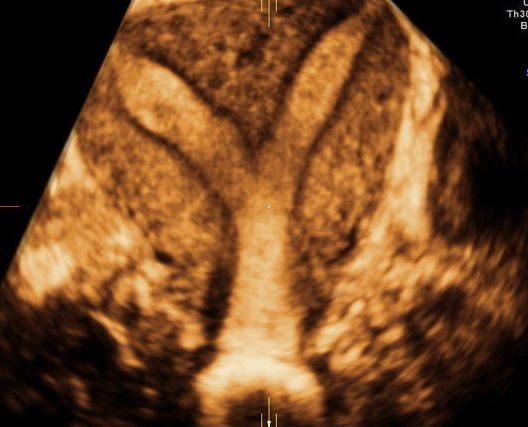

• ecografie ostetriche del I trimestre con misurazione della translucenza retronucale (NT), ecografie morfologiche (strutturali) di I e II livello, ecografie ostetriche con flussimetria doppler utero-placentare e fetale, ecografie ostetriche 3 - 4 D

Foto e video